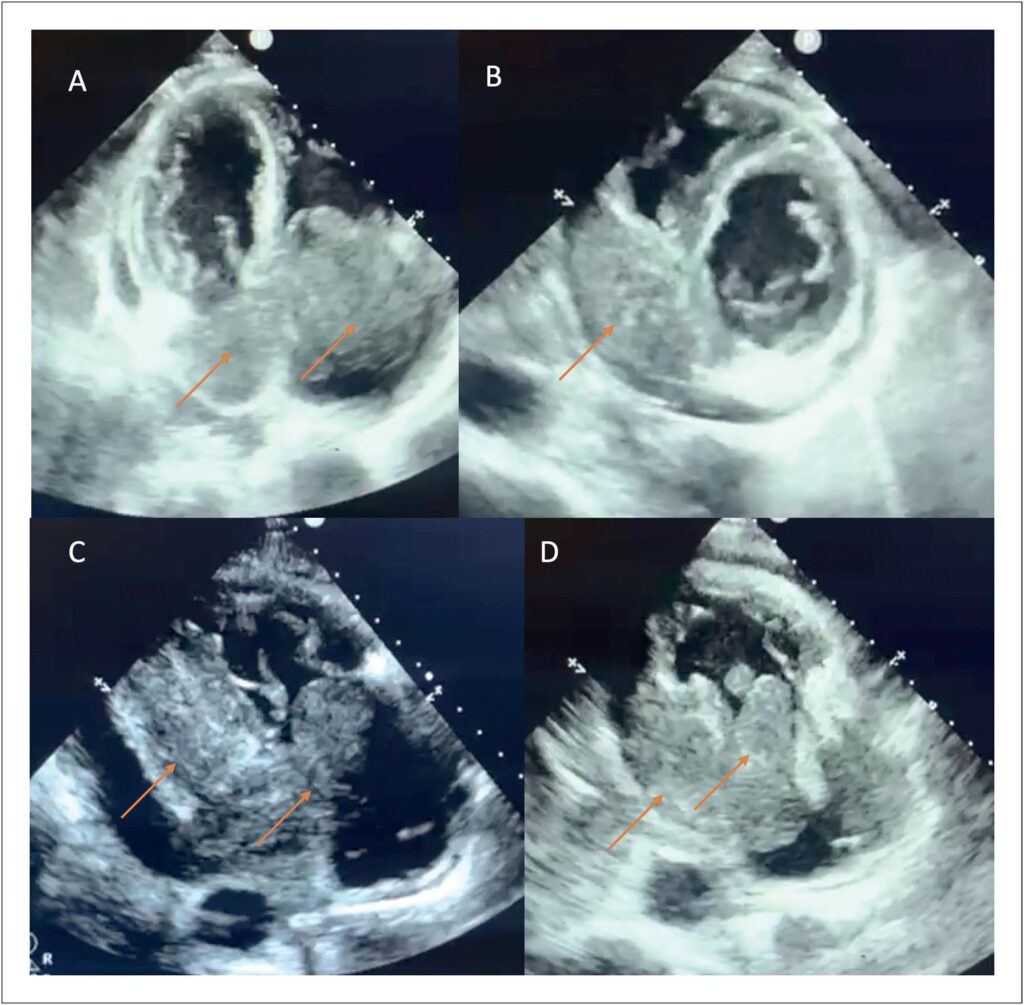

O linfoma cardíaco primário (LCP) é uma neoplasia rara e altamente letal, cuja apresentação clínica inespecífica dificulta o diagnóstico precoce. Este artigo relata o caso de um paciente idoso, previamente saudável, que apresentou tonturas e síncopes por quatro meses antes da descoberta de uma grande massa tumoral no coração. Exames de imagem, como ecocardiograma e ressonância magnética, foram cruciais para a identificação do tumor, e a biópsia confirmou tratar-se de um linfoma de células B com alta replicação. No entanto, diante da gravidade do quadro e da recusa da família em prosseguir com o tratamento, o paciente evoluiu para morte súbita duas semanas após o diagnóstico. Os tumores cardíacos primários (TCPs) são subdiagnosticados, com sintomas variados que podem incluir obstruções vasculares, arritmias e insuficiência cardíaca. Os LCPs representam apenas 1 a 2% das massas cardíacas primárias, sendo mais comuns em homens idosos. O diagnóstico é desafiador devido à ausência de sinais específicos, tornando exames de imagem e biópsias fundamentais para a confirmação da doença. O caso ilustra a complexidade do manejo dos LCPs, cuja evolução rápida limita as opções terapêuticas. A falta de sintomas específicos e a progressão silenciosa ressaltam a importância do diagnóstico precoce. A alta taxa de mortalidade reforça a necessidade de maior atenção médica para essa condição, que frequentemente leva a desfechos fatais antes da possibilidade de intervenção eficaz.